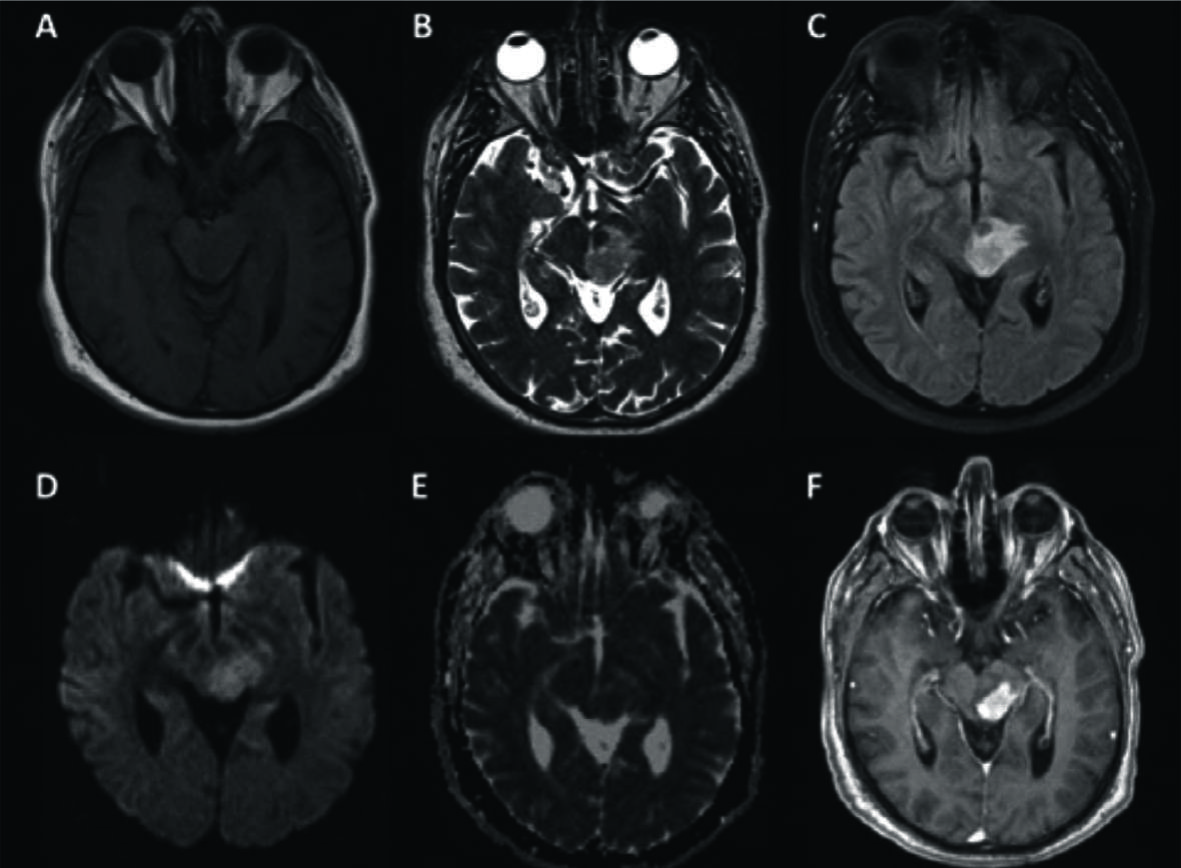

Figura 4

LPSN con necrosis central (2 pacientes).

Se muestran 2 casos de LPSN con focos tumorales que mostraron necrosis.

El primer paciente (A-C) presentó compromiso multifocal con la lesión más importante con centro hiperintenso en T2 (A), hipointenso en T1 (B) y realce en anillo periférico (C) a nivel paraventricular del lado derecho.

El 2º caso (D-F) presentó una lesión única, peri-ventricular profunda, temporal derecha, hiperintensa en FLAIR con atrapamiento del asta temporal del ventrículo lateral y escaso edema (D), isointensa en T1 (E) y realce en anillo con necrosis central (F).

Figura 5

LPSN con lesión única supra-tentorial con hemorragia.

Paciente que se presentó con episodio crítico y cuya RM mostró una lesión peri-ventricular heterogénea, hipointensa en T1 (A), hipointensa en T2 (B) con importante edema en FLAIR (C). En secuencia post-contraste se comprueba el intenso realce con contornos irregulares bien definidos (D).

La secuencia GRE T2* (E) pone en evidencia zonas de artificio de susceptibilidad que corresponden a productos de degradación de la hemoglobina y que traducen hemorragia. En difusión (F) se observa restricción periférica con marcada heterogeneidad.